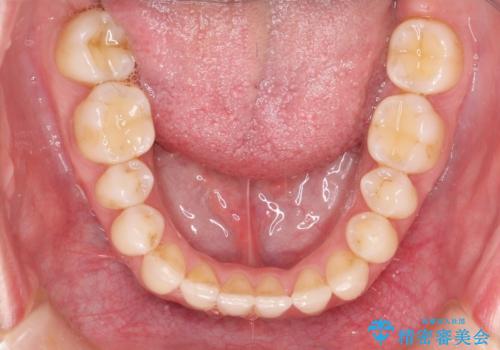

Invisalign インビザライン によるガタつき、受け口傾向の改善

奥歯の位置関係の修正は難儀することが多いマウスピース矯正ですが、割とスムーズに奥歯の位置関係の修正をすることができました。

クロスバイトもきれいになり、きれいな歯並びとなりました。